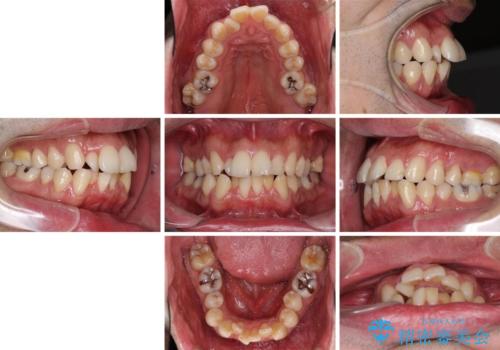

- 上下前歯のデコボコを気にして来院された患者様です。

下顎骨が顕著な左右差を持って成長したため、右側にずれている状態でした。

デコボコは抜歯をすることなく解消できる程度であったため、インビザラインにより矯正治療を行うこととしました。

インビザラインは1日22時間を目標にマウスピースを装着することで歯列を改善するものです。

そのため、上下の歯が接触することはほとんどなく、マウスピースを介した咬合において歯列矯正が進んでいきます。

この方は元々骨格的な偏位が大きかったためか、治療中に下顎骨が上顎骨よりも右外側に誘導されて、右側の奥歯が全く咬合しない状態が続いてしまいました。